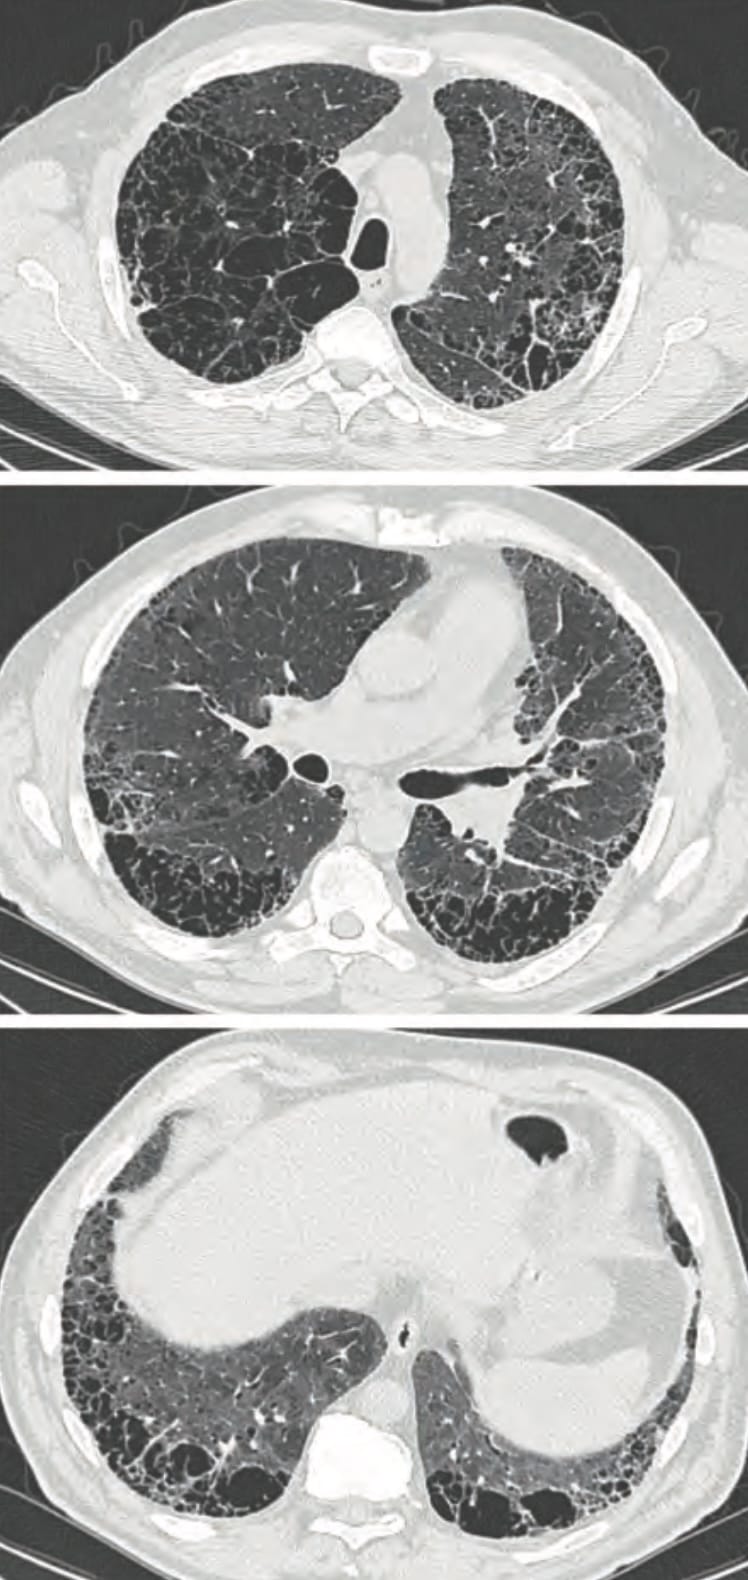

Airway-dominant phenotype

Emphysema-dominant phenotype

Mixed phenotype

We can make these distinctions on CT.

Note: bronchial wall thickening